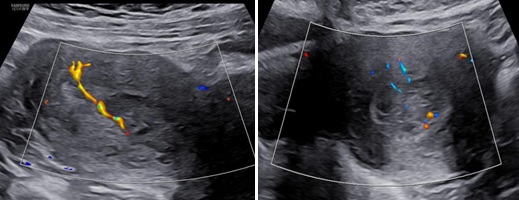

Siêu âm: Tử cung ngã trước, kích thước: 56 x 62 x 90 mm. Cơ tử cung mật độ đều, đồng nhất. Từ thành trước đoạn thân nhô vào lòng tử cung kéo dài tới cổ tử cung có khối echo dày không đồng nhất kích thước 64 x 81 x 70 mm, không rõ ranh giới với cổ tử cung và cơ tử cung. Trên Doppler màu khối tổn thương phần ở lòng tăng sinh mạch máu độ 2 và ở vùng cổ tử cung độ 4.

Hình 2: Trên Doppler màu, khối trong lòng tử cung tăng sinh mạch máu mức độ 2